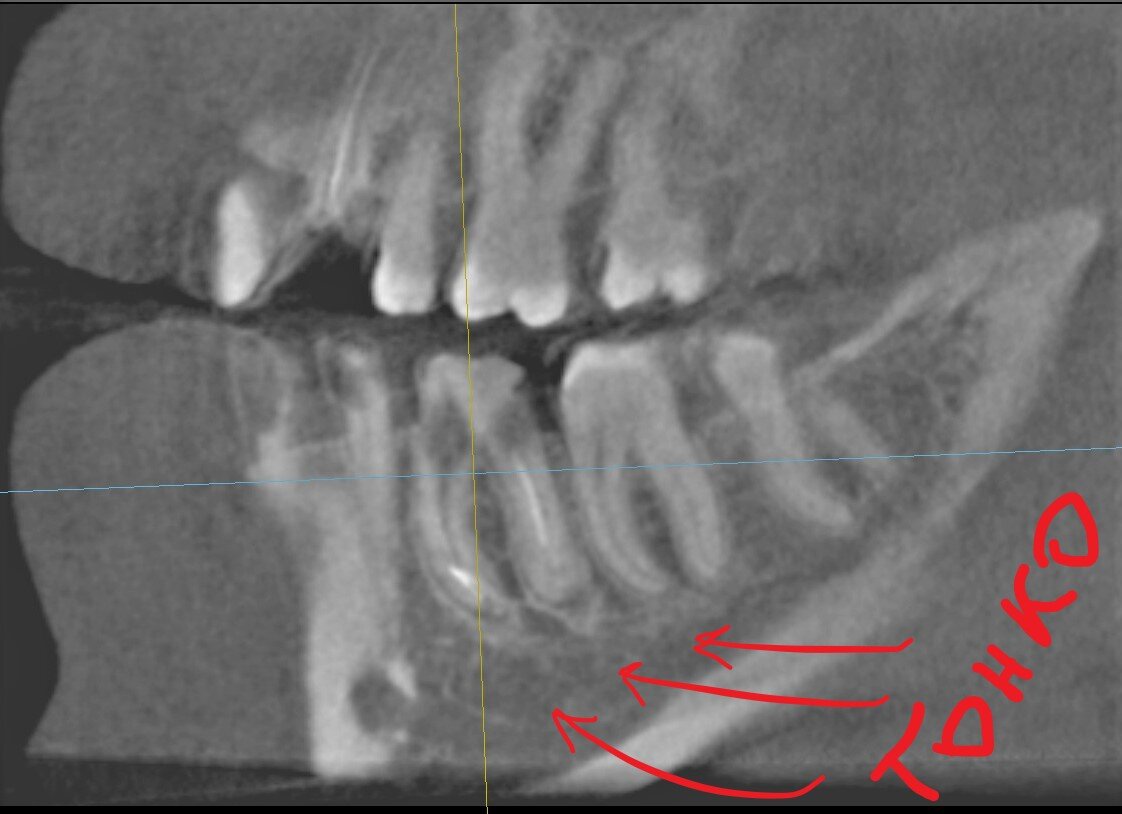

4. Дефицит кости около зуба, разный уровень костной ткани.

Видно, насколько велика разница между уровнем кости. Эти зубы удалять никто не собирается, просто для примера фото.

Имплантат должен быть полностью погружён в костную ткань. При такой картине мы должны либо "заглубиться", либо витки останутся оголёнными. Можно, конечно, сделать резекцию кости (спилить лишнее), но способ варварский и мы не можем так разбрасываться ценным материалом - собственной костью.